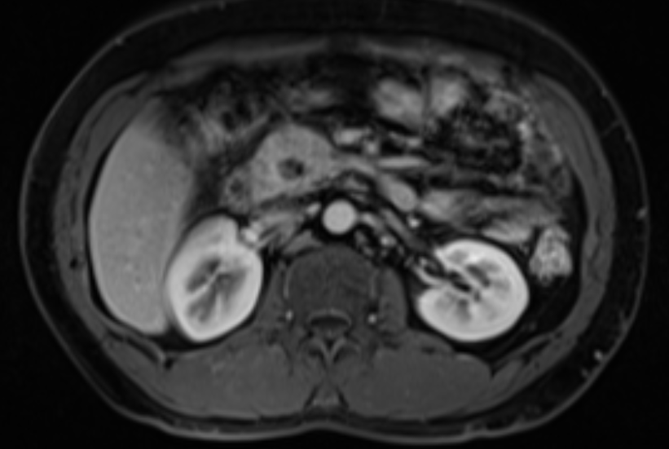

上腹部CT平扫+增强影像

通过结合各项检查结果排除禁忌症后,消化内科医护人员护送患者至内镜中心行电子胃镜+超声内镜+FNA术。手术由姚朝光主任及外院专家指导,陈丽芬副主任医师进行操作。经超声内镜检查提示“胰头见一占位,切面大小约28.5mmX25.9mm”。术中未有出血、穿孔等并发症发生,且患者未感觉穿刺部位有疼痛等不适症状,手术过程顺利。术后3天病理结果回报,在送检的组织中,只见少量破碎的胰腺腺泡上皮和炎性坏死物。黄先生及其家人也松了口气,在消化内科医护团队的精心治疗护理下,患者腹痛好转,并于5月17日康复出院。